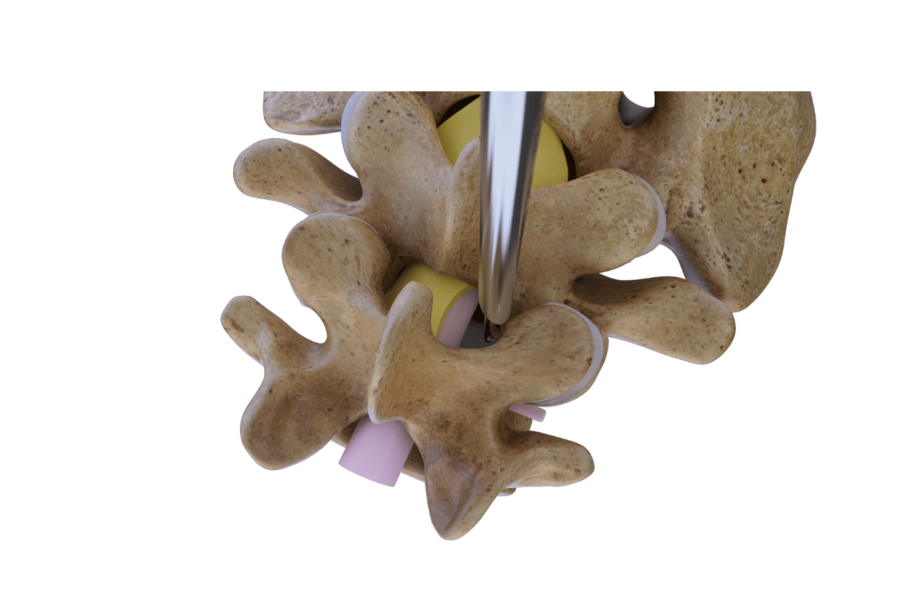

Over-the-top Technique

Contralateral decompression

Contralateral decompression for bilateral central stenosis involves an "over-the-top" technique. A unilateral approach is employed, starting with ventral resection of the spinous process to access the contralateral side. Laminotomy and partial facetectomy are performed before fully resecting the ligamentum flavum.

Care is taken to avoid excessive retraction of neural structures to minimize neurological damage.